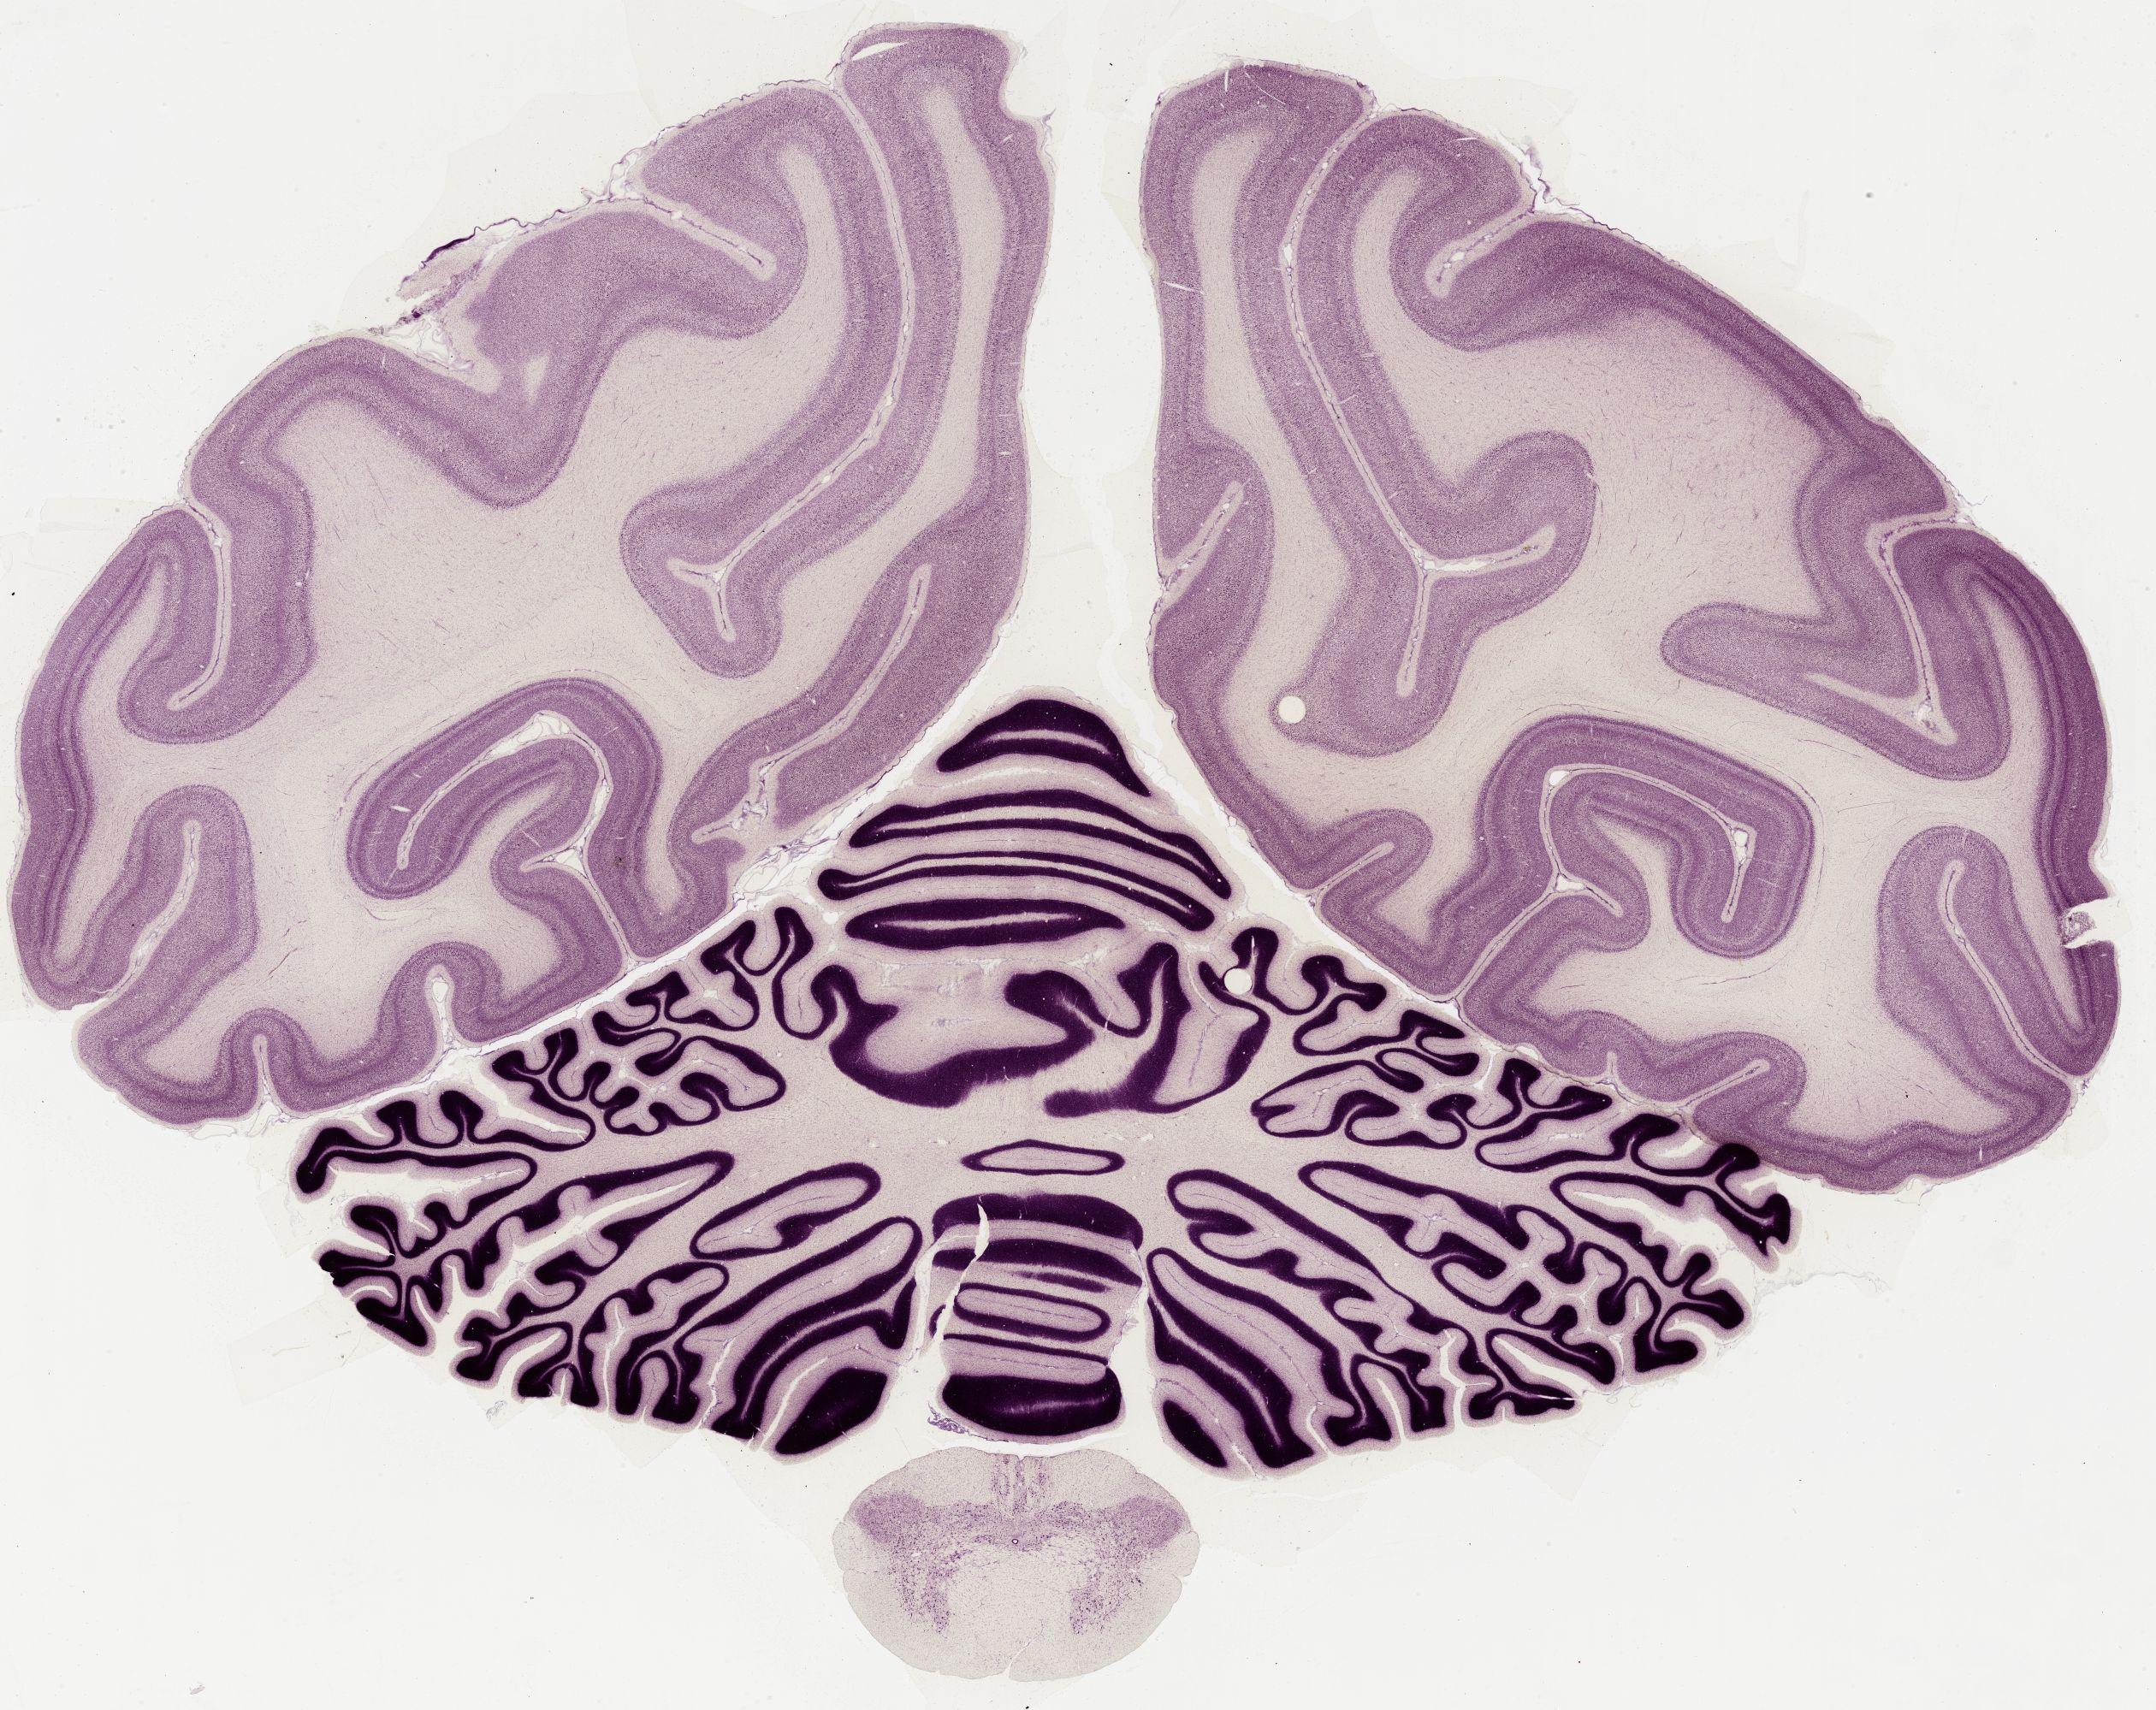

Datasets -> Macaca Mulatta -> Nissl, coronal, histo, Whole-Brain, adult

[ Metadata ]   ·   Source: Edward G. Jones

0650 - labeled